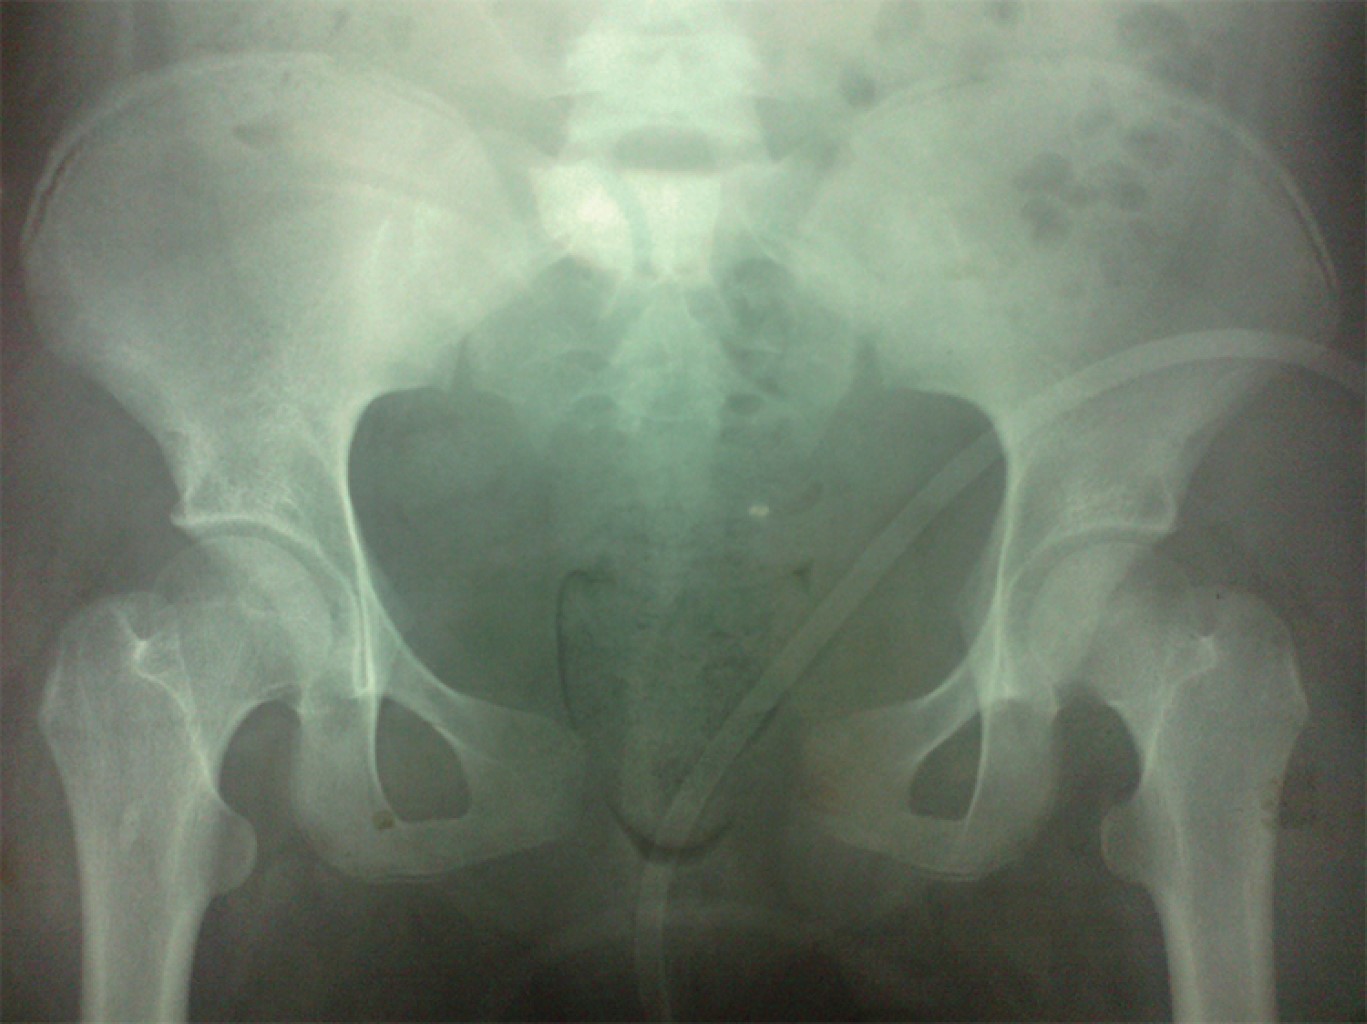

Radiológicamente, se detecta presencia de lesión a nivel de la sínfisis del pubis con una separación de 5.5 cm, se advierte falta de fusión a nivel de ambas crestas iliacas, de igual manera en la tomografía axial computarizada de reconstrucción se corrobora la lesión púbica y lesión a nivel de las articulaciones sacroiliacas en los ligamentos anteriores (Figuras 1 y 2).

Motivo por el cual se procedió a iniciar manejo quirúrgico mediante la realización de una reducción abierta y colocación de dos placas DCP (placas de compresión dinámica) 3.5 mm de cinco y cuatro orificios en la superficie anterior y superior del pubis, respectivamente como medio para estabilizar el anillo pélvico. La lesión de la articulación sacroiliaca se manejó de forma conservadora (Figuras 3 y 4), no se presentó ninguna complicación en el transoperatorio y evolucionó de la misma manera durante su estancia hospitalaria.